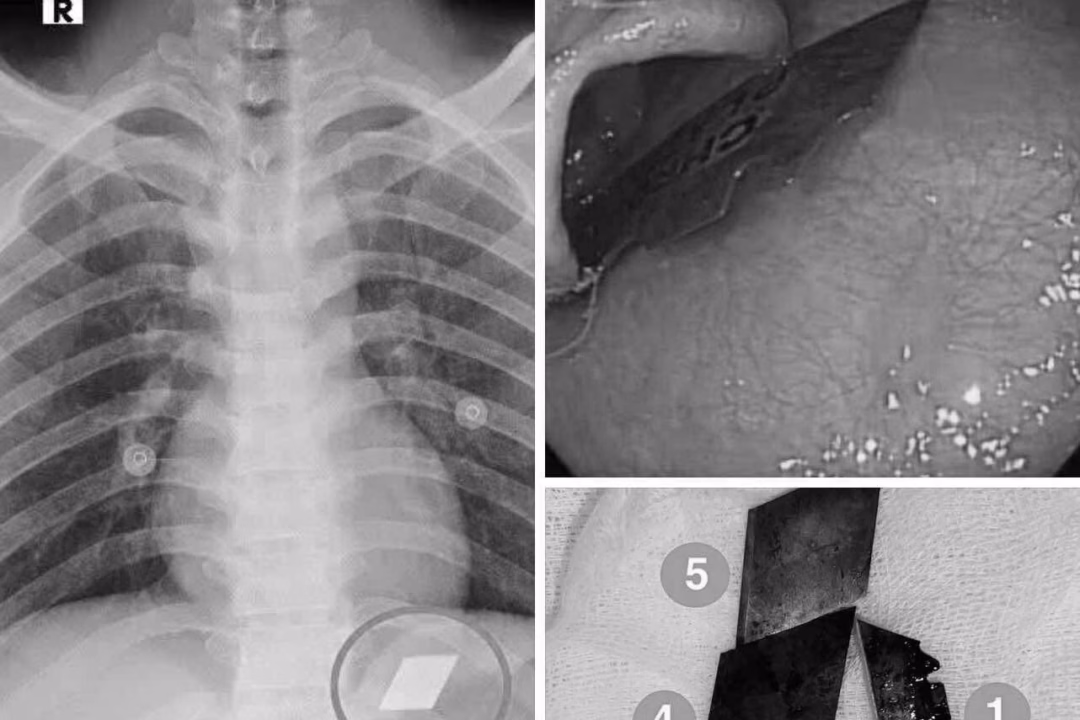

Ngày 10/7, Khoa Hồi sức cấp cứu của Bệnh viện Đa khoa Bình Dương đã tiếp nhận một trường hợp cấp cứu đặc biệt hiếm gặp. Bệnh nhân P.V.L, 26 tuổi, được đưa vào viện trong tình trạng nuốt nhiều dị vật kim loại sắc nhọn, bao gồm dao rọc giấy và dao lam.

Qua quá trình thăm khám và chụp X-quang, các bác sĩ đã phát hiện ra các dị vật cản quang tại vị trí dạ dày của bệnh nhân. Ngay lập tức, bệnh nhân được chỉ định tiến hành nội soi cấp cứu để gắp bỏ những dị vật này. Với sự phối hợp chặt chẽ giữa ê-kíp nội soi và gây mê, các bác sĩ đã thành công trong việc gắp 4 lưỡi dao rọc giấy ra khỏi dạ dày và một phần lưỡi dao lam mắc tại vùng hạ họng – miệng thực quản của bệnh nhân.

Sau khi hoàn thành thủ thuật, bệnh nhân được theo dõi sát và đã ổn định sức khỏe, xuất viện trong tình trạng an toàn. Theo bác sĩ Phan Lê Quốc Du, trưởng Khoa Thăm dò chức năng của Bệnh viện Đa khoa Bình Dương, các dị vật sắc nhọn trong đường tiêu hóa đòi hỏi phải được can thiệp nội soi kịp thời. Nếu không được lấy ra kịp thời, những dị vật này có thể gây thủng thực quản, thủng ruột, dẫn đến biến chứng nặng nề, thậm chí tử vong.